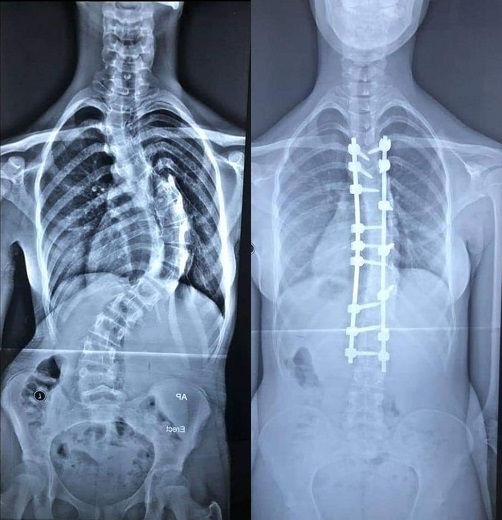

أطباء الكفيل التخصصي ينجحون بإستعادة إستقامة ظهر فتاة عشرينية تعاني من تحدب في العمود الفقري

اعلن فريق طبي في مستشفى الكفيل التخصصي بكربلاء نجاحه بمعالجة مريضة عشرينية تعاني من تحدب شديد في العمود الفقري بعملية نوعية أستعادة من خلالها استقامة عمودها الفقري.

وقال أختصاصي جراحة الجملة العصبية بالمستشفى، الطبيب السوري د. وائل قاسم، في حديث صحفي، أن فريق طبي برئاستنا نجح بمعالجة فتاة تبلغ من العمر (18) عام تعاني من تحدب شديد في العمود الفقري وغير قادرة على الوقوف باستقامة مثل الاشخاص الاعتياديين.

وبين قاسم، بعد دراسة حالتها الصحية ادخلت الى صالة العملية واجرينا لها عملية استغرقت قرابة الـ(6) ساعات تم خلالها تعديل الانحراف باستخدام تثبيت الفقرات وقطع جزء من العمود الفقري لأجراء التعديل.